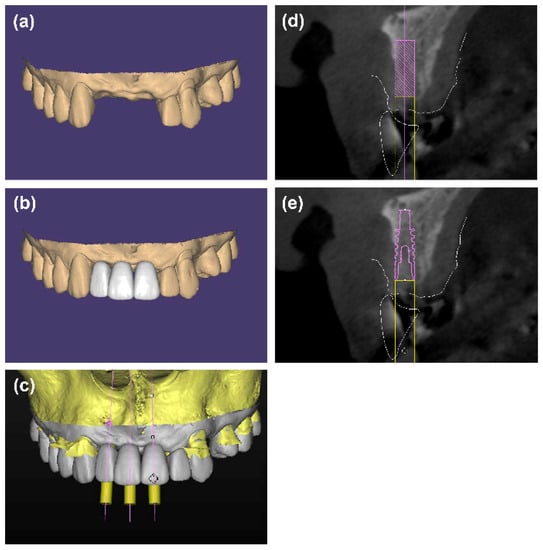

Test group: the surgical procedure was similar to the control group. However, a digital simulation of bone graft contour aiming at reconstructing the ideal alveolar contour and ensuring enough bone for implant placement, was performed based on the pre-operative CBCT data before surgery (Mimics 20.0, Materialise, Leuven, Belgium). The virtual bone graft contour was over-thickened to achieve 1.5 mm of over-augmentation, after which a two-piece tooth-supported surgical template was designed by Mimics software and manufactured by 3D printing technology (ProJet MJP 2500Plus, 3D Systems, Inc., Rock Hill, SC, USA). During the surgery, the i-PRF block was placed into the defect under the guidance of the surgical template to form a customized i-PRF block. A collagen membrane was covered over the customized i-PRF block and fixed with several 4 mm titanium pins (Figure 3).

Figure 3.

(a) Digital simulation of the bone graft contour before surgery. (b) A two-piece surgical template, which consists of two parts: the coronal part (red) for retention and the labial part (green) for shaping the bone grafts, was fabricated based on the digital model. the template can be removed without disrupting the graft material. (c,d) The labial defect could be observed. (e) Particulate bone substitutes were mixed with i-PRF. (f,g) The mixture of i-PRF and particulate bone substitutes was placed into the defect under the guidance of the surgical template. (h) The customized i-PRF block was covered with a collagen membrane and fixed with pins. (i) Radiographic cone-beam CT view immediately after wound closure. (j) Radiographic cone-beam CT view at 6 months.